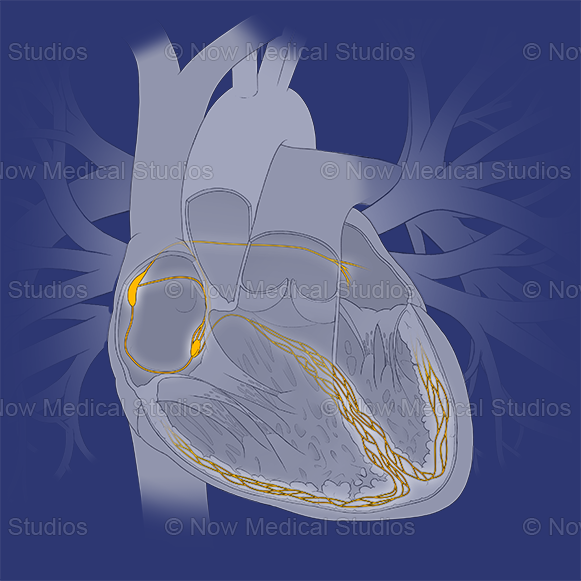

Heart conducting system. Stock medical illustration

A medical illustration of the cross-sectional and internal anatomy of the heart. Here you can see the highlight of the heart's conduction system, with anatomy that includes: the sinoatrial node (also known as the pacemaker), the internodal pathway, atrioventricular node, Bundle of His (or atrioventricular bundle), and Purkinje fibres.

Here you can also see other anatomical landmarks of this major cardiovascular organ; such as the ascending aorta, brachiocephalic trunk, left common carotid artery, left subclavian artery, left pulmonary artery, left and right pulmonary veins, left and right atrium, superior and inferior vena cava, aortic valve, tricuspid valve, mitral valve, chordae tendineae, papillary muscle, intraventricular septum, fossa ovalis, epicardium, myocardium, endocardium, and more.

These illustrations were created on a transparent background, giving you full flexibility to use them with your brand colours.

A medical illustration of the cross-sectional and internal anatomy of the heart. Here you can see the highlight of the heart's conduction system, with anatomy that includes: the sinoatrial node (also known as the pacemaker), the internodal pathway, atrioventricular node, Bundle of His (or atrioventricular bundle), and Purkinje fibres.

Here you can also see other anatomical landmarks of this major cardiovascular organ; such as the ascending aorta, brachiocephalic trunk, left common carotid artery, left subclavian artery, left pulmonary artery, left and right pulmonary veins, left and right atrium, superior and inferior vena cava, aortic valve, tricuspid valve, mitral valve, chordae tendineae, papillary muscle, intraventricular septum, fossa ovalis, epicardium, myocardium, endocardium, and more.

These illustrations were created on a transparent background, giving you full flexibility to use them with your brand colours.

A medical illustration of the cross-sectional and internal anatomy of the heart. Here you can see the highlight of the heart's conduction system, with anatomy that includes: the sinoatrial node (also known as the pacemaker), the internodal pathway, atrioventricular node, Bundle of His (or atrioventricular bundle), and Purkinje fibres.

Here you can also see other anatomical landmarks of this major cardiovascular organ; such as the ascending aorta, brachiocephalic trunk, left common carotid artery, left subclavian artery, left pulmonary artery, left and right pulmonary veins, left and right atrium, superior and inferior vena cava, aortic valve, tricuspid valve, mitral valve, chordae tendineae, papillary muscle, intraventricular septum, fossa ovalis, epicardium, myocardium, endocardium, and more.

These illustrations were created on a transparent background, giving you full flexibility to use them with your brand colours.